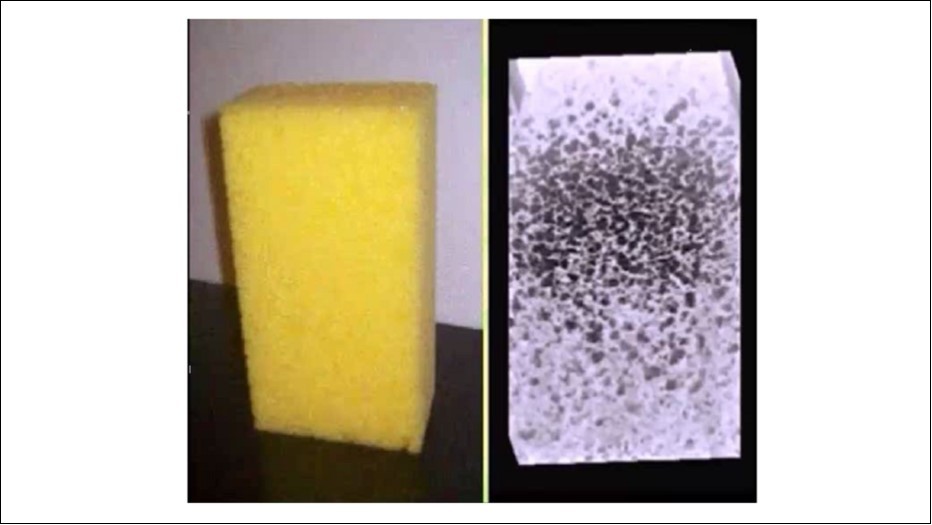

Measurement of 26 different transducer models from five manufacturers was performed using the RVP. The RVP for grayscale resolution consists of an artificial water filled foam sponge submersed in a water filled tank, Figure 1.

Figure 1.Random Void Phantom: Water-filled artificial foam immersed in a water tank. The 3D image shows the ultrasound image of the sponge acquired with a matrix probe.

Synthetic foam has an acoustic absorption similar to echo free cysts (voids) in living tissue. The voids are filled with pure water being free of reflective contaminants. The remaining background noise in the voids is caused only by the side and grating lobes. The tolerances of the foam inhomogeneities for maximum acoustic contrast are in the range +/- 1.5 dB 1, 6.

If cysts (voids) are absolutely echo free, all side lobes being generated at the edges of the piezoelectric transmitter and the receiver will appear inside the cyst. Artificial foam in the form of a sponge submersed in water (RVP) is suitable for quantifying the grayscale resolution of an ultrasound probe. The sound attenuation in the foam behaves as in living tissue; the cavities (voids) are free of inclusions. The acoustic contrast thus largely depends on the side lobes.

The RVP model as described above is ideal for such a purpose with an attenuation that comes very close to echo free cysts (voids) in living tissue. When the voids are filled with pure water they are free of reflective impurities and only side and grating lobes can be the cause of apparent reflections within the voids. The number of side lobes ultimately determines image quality, or in other words the "acoustic contrast".